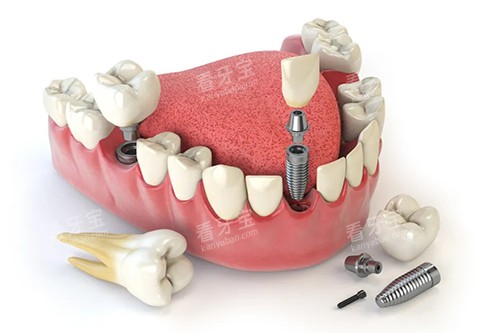

种植体是种植牙的核心部件,其质量直接影响到种植牙的使用寿命和结果。

杭州植成口腔与多家国内外老牌的种植体品牌合作,为患者提供多种优质的种植体材料。

这些种植体材料具有良好的生物相容性,能够与牙槽骨紧密结合,形成稳固的骨结合。

例如,一些种植体采用了特殊的表面处理技术,能够促进骨细胞的生长和附着,加快骨结合的速度。

同时,这些种植体还具有良好的机械性能,能够承受较大的咀嚼力,确保种植牙的稳固耐用。